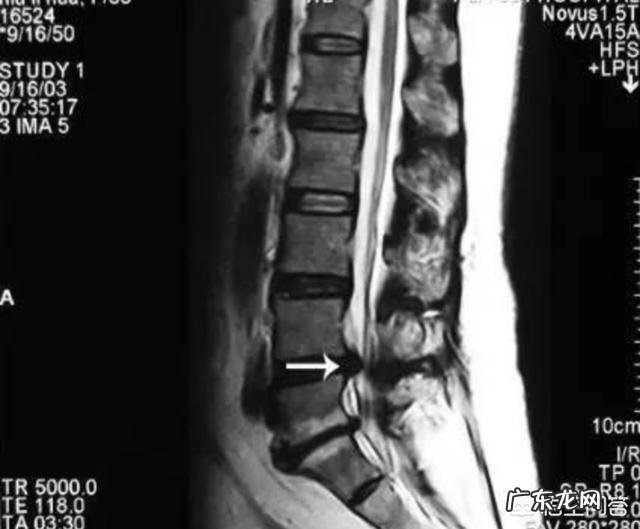

腰椎间盘突出压迫坐骨神经痛 , 可以自愈吗?腰椎间盘突出症的恢复 , 一定离不开身体的自愈能力 , 不管用什么方法 , 自愈能力一定是起到最主要作用的 , 是一切康复方法的基础!

确诊是否腰椎间盘突出症?腰椎间盘突出压迫神经造成的神经痛有自己的特点 , 在出现疼痛的时候 , 一定要先鉴别诊断明确 , 不要有腰腿疼症状 , 做CT有椎间盘突出就确诊!

L4-5椎间盘突出症 , 压迫L5神经 , 会造成下腰部疼痛 , 臀部外侧 , 大腿外侧 , 小腿外侧 , 脚面 , diyi和第二脚趾附近的疼痛和麻木!

L5-s1椎间盘突出症 , 压迫S1神经 , 会造成下腰部疼痛 , 臀部后侧 , 大腿后侧 , 小腿后侧 , 小脚趾外侧的疼痛和麻木!